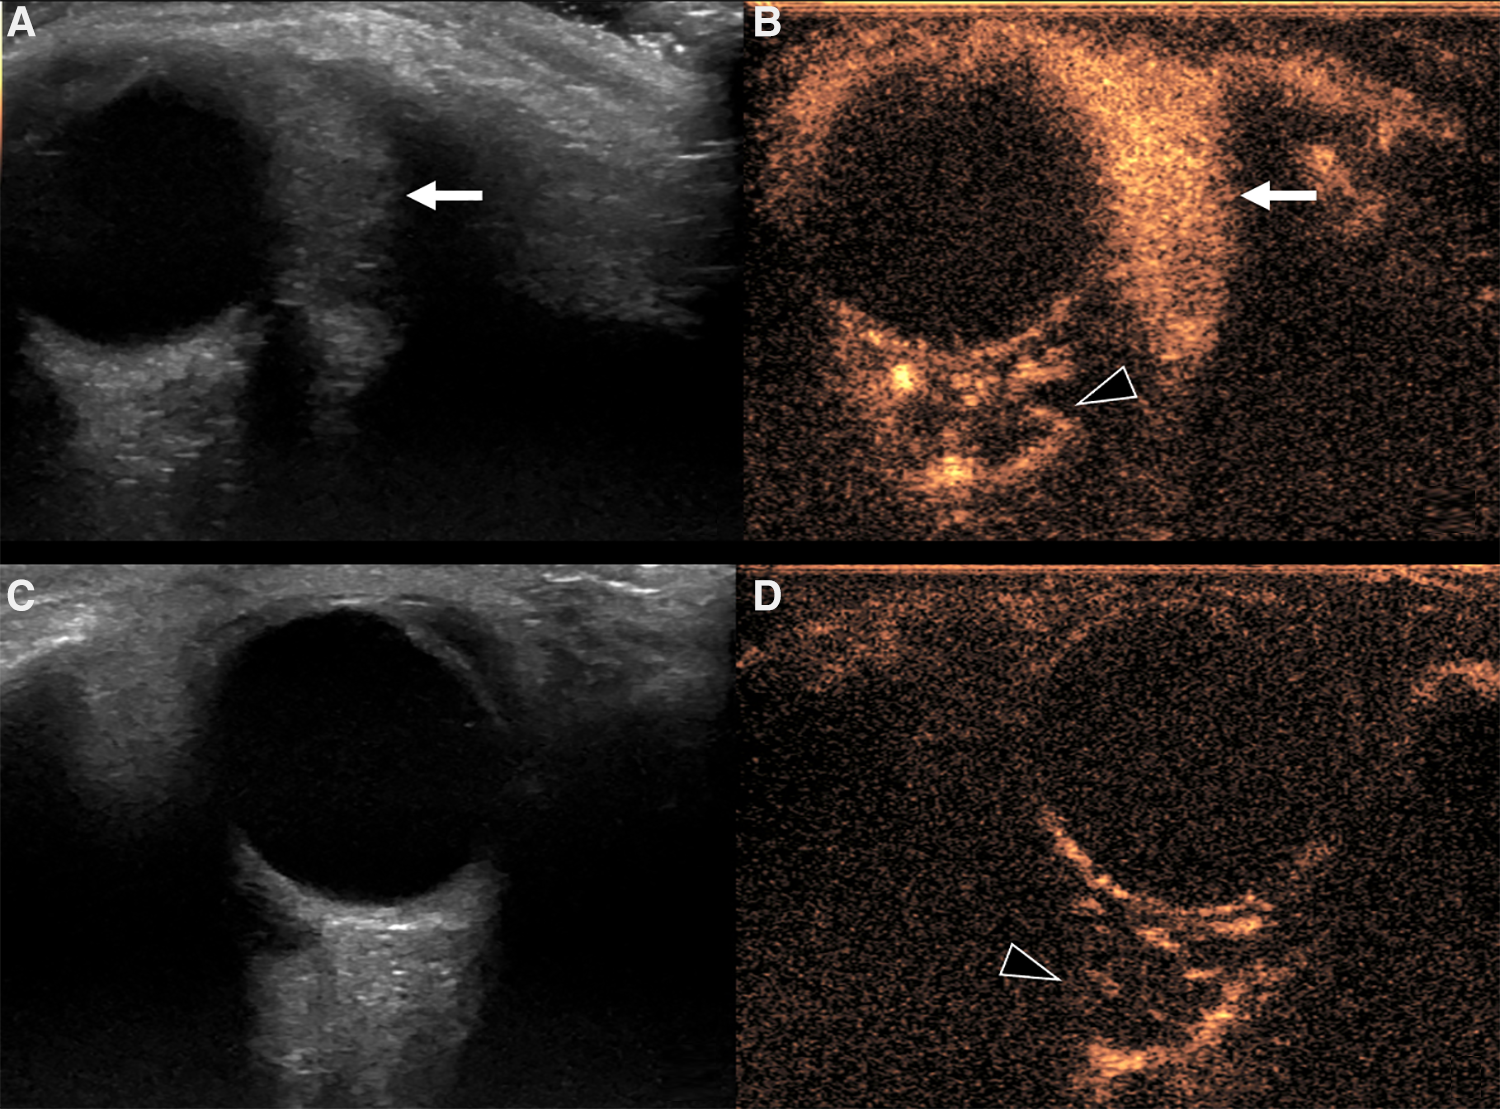

Despite the different pathogenesis, clinical presentation and genetics, CH and IH have almost the same imaging characteristics, particularly during the proliferative phase. However, CHs are more likely to have aneurysms, larger venous components, intravascular thrombi and even high flow velocity at birth, compared to their infantile counterpart (19), ancillary findings that must be carefully be searched for. US demonstrates a well-demarcated tumor with variable echogenicity and high vascularity, showing more than 5 vessels/cm with high flow velocities at Color Flow Doppler during the proliferating phase (20) (Figure 2). During the involuting and involuted phases, flow velocity and vessel density will decrease. Due to its considerable abilities in the assessment of intra-lesional blood flow, CEUS is making its way as a powerful additional tool in the assessment of orbital space-occupying lesions (21, 22). At CEUS hemangiomas are hyper-enhancing during both the early and late arterial phase. Enhancement of IHs starts as a peripheral nodules and then progressively expands in a centripetal pattern and completely fills the lesion (Figure 3). During the delayed phase, hemangiomas keep showing sustained enhancement relative to surrounding tissues.

Figure 3. Us and CEUS of a left orbital infantile hemangioma (IH) in a 3-year-old girl: the patient was initially referred for a forehead red macule on the left and a slight ipsilateral orbital proptosis. (A,B) Depict US of the left orbit, while US of the right orbit is represented in (C,D). At B mode US (A) a uniformly hyperechoic mass was discovered (white arrow) with rapid and complete enhancement at CEUS (B, white arrow) Of note, left retrobulbar vessels appeared more prominent than the contralateral side (arrowhead in B and D, respectively). The orbital mass showed the same US characteristics of the IH of the forehead (not shown).